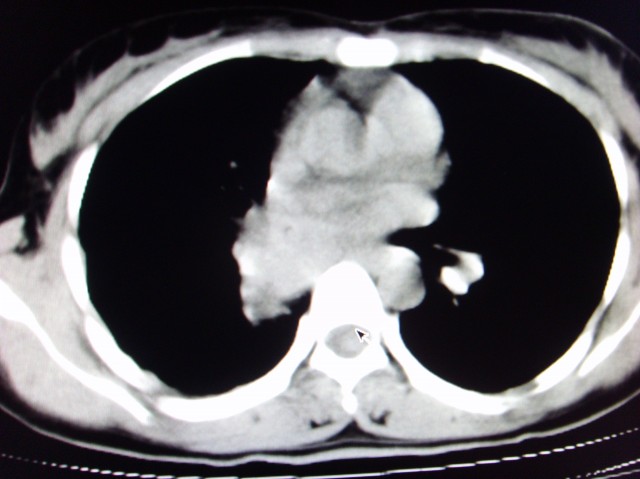

标题: CT7125:中央性肺Ca. [打印本页]

标题: CT7125:中央性肺Ca.

典型 中央型ca伴双肺、淋巴结转移

典型 中央型ca伴双肺、淋巴结、胸膜转移

右下中心型肺癌伴双肺转移、纵隔淋巴结转移,癌性淋巴管炎可能性大

支持楼主的中央型肺癌,肺内,纵隔内淋巴结转移

典型的中央型ca伴双肺、纵隔淋巴结转移.

支持楼主诊断:中央型肺癌,肺内,纵隔内淋巴结转移。

典型--右下中心型肺癌伴双肺转移、纵隔淋巴结转移,癌性淋巴管炎可能性大

中心型肺癌伴双肺转移及纵隔淋巴结转移,癌性淋巴管炎

经典病历,肿块。肺内转移、淋巴结转移。胸膜仗义

典型的中央型ca,肿快和肺门分界不清,肿快边界模糊,呈毛刺状。伴淋巴结转移。